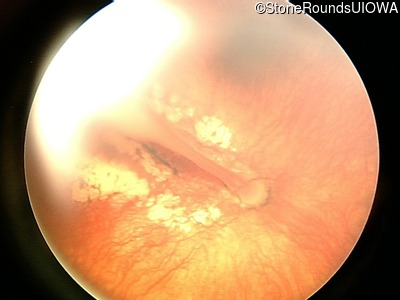

Fundus Photography - Right - 20/500

Exemplar